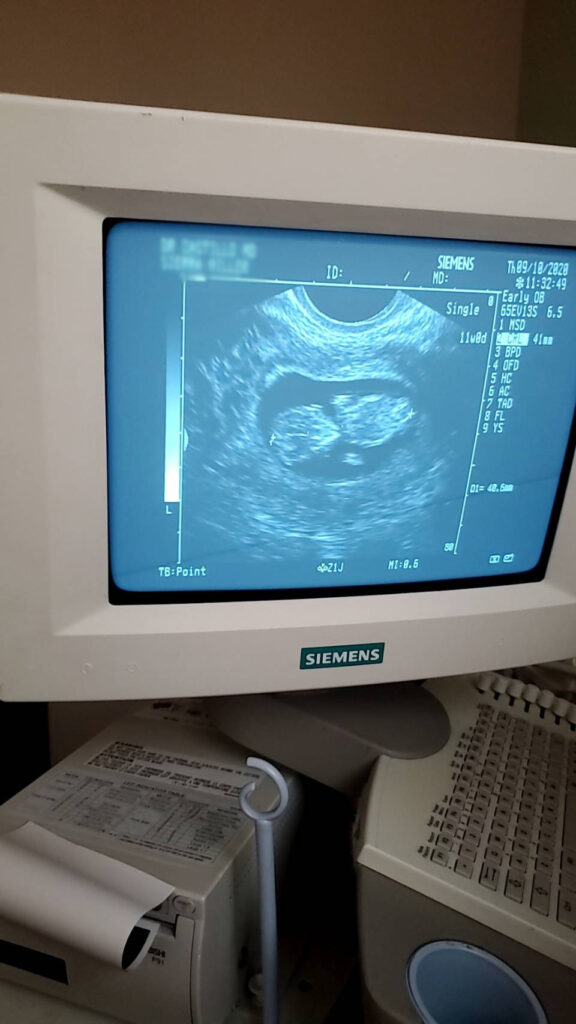

Baby超音波紀錄 : 11週 Posted on September 13, 2020 by yourtesttubebaby 11週的小baby就是長的這樣的! 寶寶營養很好所以長得很快而且蠻大隻的! !😄 ☀ 網站上每位小寶貝都是我們的成功案例,照片皆經父母親許可使用 ( 若未經允許請勿轉載 ) ☀ Posted in Uncategorized